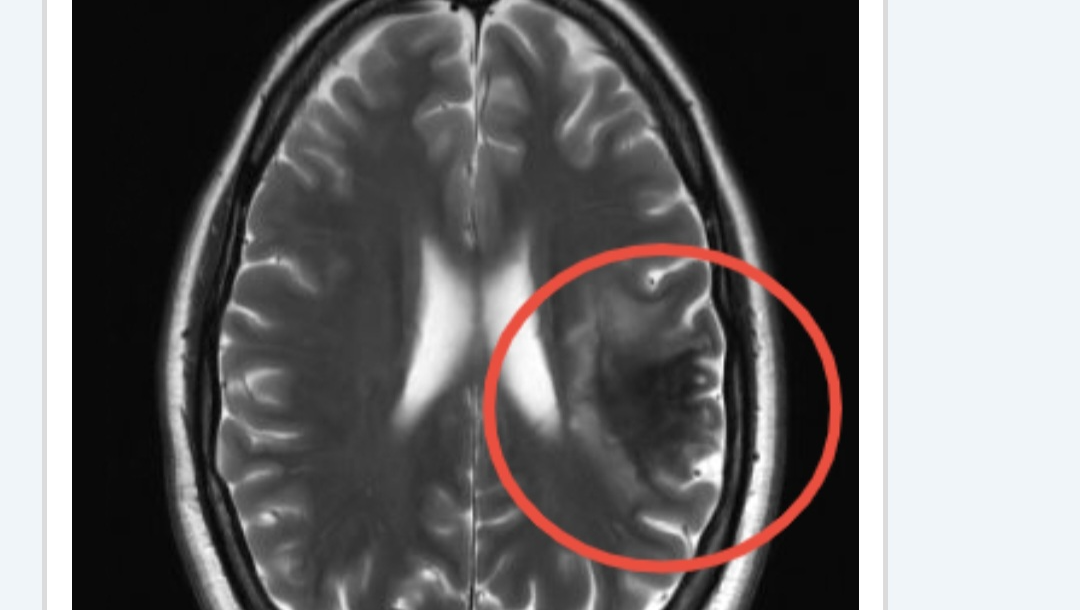

Hey guys, as most of yall know, I had a stroke in September, four months after daddy Phil passed away. I got my check up and my neurologist says I about 6 more months for my brain to heal...my right side isn't working like it should, my speech is still bad and I have a hard time still understanding tasks, im definitely getting better but it's a slow process. Me and Biscuit have been doing our best to take care of ourself, but once again we are asking for a little help until I get well again to go back to work...the universe is definitely putting me to the test, but I will not give up and throw in the towel! Thank yall and we love yall to the moon..and thank you for rooting for us with everything we've gone through!